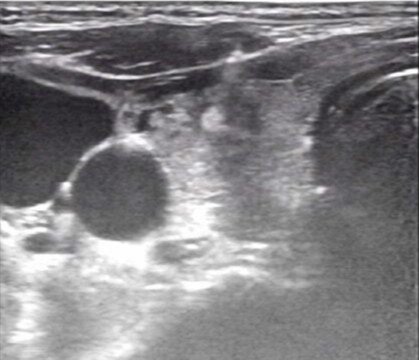

超声引导下的甲状腺结节细针穿刺活检术(US-FNAB)是指在高频超声引导下,应用无菌穿刺针(通常22-25G的甲穿专用针)穿刺甲状腺结节可疑部位,抽取部分结节成分送细胞学病理检测的一种鉴别甲状腺良恶性的方法。甲状腺结节是临床上最常见的甲状腺病变。超声在甲状腺结节评估中具有很高的敏感性及特异性,然其仅能对甲状腺结节的实现初步评估,无法给予明确的定性诊断。目前超声引导下细针穿刺活检已成为甲状腺结节评估的金标准。一方面提供甲状腺结节的重要信息如回声情况、边界、形状,有无钙化、血流情况等。另外一方面赋予细针穿刺活检精确定位的优势,极大降低了假阴性穿刺及取样的不满意情况。